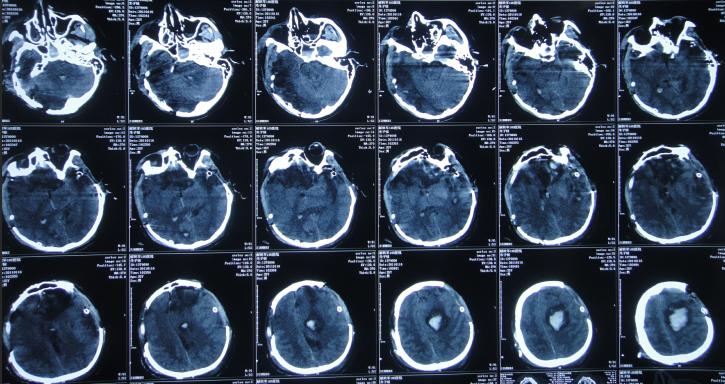

患者于2011年1月14日晚11点,意外发生车祸当即昏迷,120救护车将其送往第1家的安徽省合肥市的某三甲医院,查头颅CT:重度颅脑损伤,脑出血( 图-1 )。

图-1: 2011年1月15日头颅CT